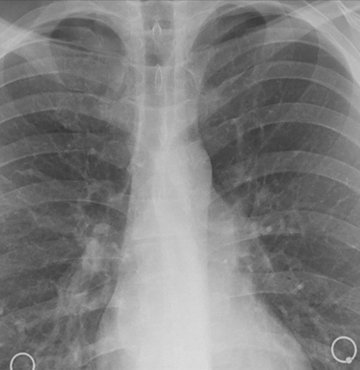

Türk Toraks Derneği Genel Başkanı Prof. Dr. İtil, TürkiyeTürk Toraks Derneği Genel Başkanı Prof. Dr. İtil, Türkiye'de yılda 35 bin kişinin akciğer kanseri tanısı aldığına dikkati çekerek "Ülkemiz, erkeklerde 100 bin kişide 41,7 oranı ile dünyada akciğer kanserinin en çok saptandığı ülkelerden biri" dedi